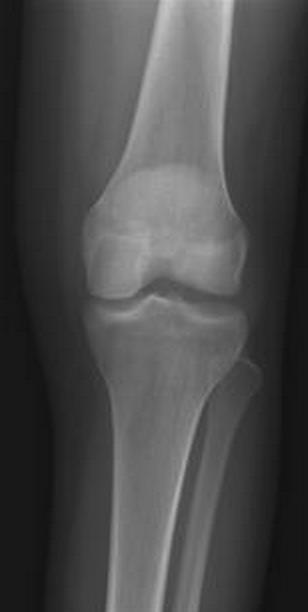

An 18-year-old man sustains a twisting injury to the left knee while playing football. An MRI scan is shown in Figure 48. What is the most likely diagnosis?

MRI scan shows a displaced, bucket-handle lateral meniscus tear. The sagittal view shows the typical “large anterior horn” sign, or “double meniscus” sign in which the displaced bucket-handle fragment appears just anterior to the native anterior horn of the lateral meniscus. The presence of the fibula on the sagittal view confirms this as the lateral compartment. The image is lateral and the cruciate ligaments are not visualized. The articular cartilage shown does not demonstrate an osteochondral lesion.